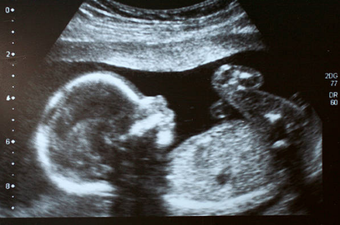

A baby in South America was born with her own twin growing inside of her